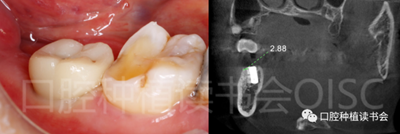

5.4.3 術(shù)后第10周,47戴入最終種植冠,X片確認(rèn)基臺(tái)就位準(zhǔn)確(圖25),以30N.cm扭矩旋緊基臺(tái)螺絲(圖26)。

5.4.4 種植冠封閉螺絲孔后,調(diào)合,拋光,完成最終修復(fù)(圖27);戴牙前CBCT顯示:種植體頰側(cè)骨板厚度為2.88mm;47種植冠獲得了良好的穿齦輪廓,并維持了正常的頰側(cè)牙弓輪廓。